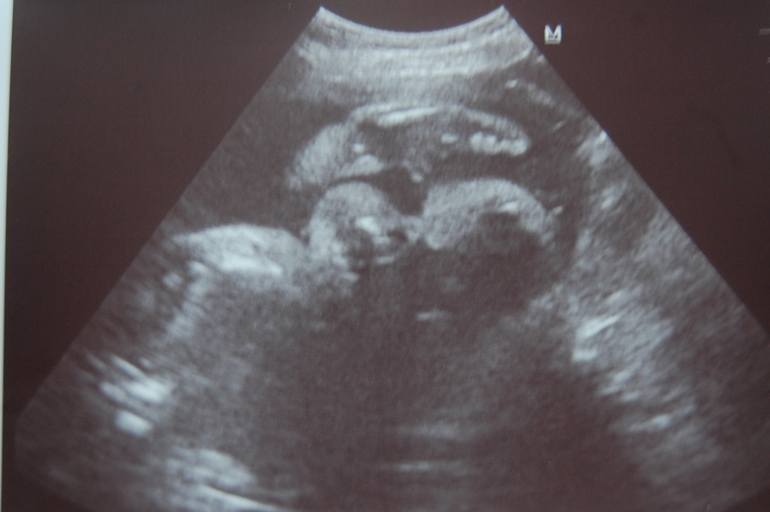

Результаты: УЗИ, КТГ, доплера, скринингаСрок сегодня 30+2,была на УЗИ,так как меня напугали,что с малышом из-за моего низкого гемоглобина могут быть проблемы... а у нас-то всё хорошо)))сынуличка мой такой классный.Весит моё счастье 1800,по развитию опережаем на 2 недели.ЧСС-145 длина ШМ-45мм, зрелость плаценты 0-1...в сердечке у нас в 20 недель было что-то,мне сказали пройдет и вот сегодня увидели в сердечке гиперэхогенное включение 3*2,но врач говорит,что это ничего страшного.Пытались мы сделать фото,а у малыша моего около личика и руки и ноги и пуповина,в общем сделали как могли)))такой смешной,я видела,как он пузырек один пустил)))показали мне наше хозяйство...а там прям такое хозяйственное хозяйство,жаль не сделала она фото,нашему папе показать))))эх,в общем я после УЗИ поехала в стационар,и всю дорогу я улыбалась как блаженная)))в стационаре ничего не сказали,прийти в понедельник надо будет,что он скажет или не скажет не знаю,но по идее все мои анализы должны быть готовы уже.Муж у меня уезжает на эти выходные отдыхать,я не поеду,1-ему и от меня пора бы отдохнуть,чисто в мужской компании и 2-холодно уже ехать куда-либо,а тем боле на берег моря.А сколько ваши малыши весят на моем сроке?ну и фоточку своего пупса покажу.Губастик мой шладенький

и вы растите здоровенькими и крепенькими.Ну мне вот сказали,что по идее с 30й недели малышик будет набирать по 40гр в сутки,посмотрим)))